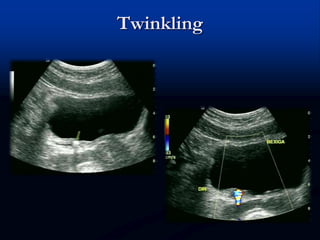

Twinkling

 Descrito em 1996 por Rahmouni e cols.

 Artefato de cor posterior a estrutura estacionária

fortemente reflexiva, preferencialmente de

superfície irregular ou granular – como cálculos

renais

 Mais comum com PRF baixo

 O filtro de parede pode excluir o sinal

Twinkling  Descrito em1996 por Rahmouni e cols.  Artefato de cor posterior a estrutura estacionária fortemente reflexiva, preferencialmente de superfície irregular ou granular – como cálculos renais  Mais comum com PRF baixo  O filtro de parede pode excluir o sinal

• #69 Twinkling artifact. (A) Longitudinal image of bladder shows typical ureterovesical junction stone (arrow) with posterior shadow. (B) Transverse CDUS image of bladder shows right ureteral calculus (arrow) and twinkling artifact generated posteriorly (arrowheads). (C) Power Doppler also generates signal (arrowheads) posterior to stone. (D) Corresponding Doppler spectrum through twinkling color shows equal amplitude noise above and below baseline. Same spectral tracing is generated whether color or power Doppler images “twinkle.” (From Campbell Campbell SC, Cullinan JA, Rubens DJ. Slow flow or no flow? Color and power Doppler US pitfalls in the abdomen and pelvis. Radiographics 2004;24:497–506; with permission.) Twinkling artifact in carotid. (A) Twinkling artifact (arrowheads) occurs behind calcifications (arrows) in atherosclerotic plaque, not to be mistaken for ulceration and disturbed flow. (B) Calcifications (arrows) are better visualized on gray-scale image. (From Campbell SC, Cullinan JA, Rubens DJ. Slow flow or no flow? Color and power Doppler US pitfalls in the abdomen and pelvis. Radiographics 2004;24:497–506; with permission.)

• #70 Twinkling artifact. (A) Longitudinal image of bladder shows typical ureterovesical junction stone (arrow) with posterior shadow. (B) Transverse CDUS image of bladder shows right ureteral calculus (arrow) and twinkling artifact generated posteriorly (arrowheads). (C) Power Doppler also generates signal (arrowheads) posterior to stone. (D) Corresponding Doppler spectrum through twinkling color shows equal amplitude noise above and below baseline. Same spectral tracing is generated whether color or power Doppler images “twinkle.” (From Campbell Campbell SC, Cullinan JA, Rubens DJ. Slow flow or no flow? Color and power Doppler US pitfalls in the abdomen and pelvis. Radiographics 2004;24:497–506; with permission.) Twinkling artifact in carotid. (A) Twinkling artifact (arrowheads) occurs behind calcifications (arrows) in atherosclerotic plaque, not to be mistaken for ulceration and disturbed flow. (B) Calcifications (arrows) are better visualized on gray-scale image. (From Campbell SC, Cullinan JA, Rubens DJ. Slow flow or no flow? Color and power Doppler US pitfalls in the abdomen and pelvis. Radiographics 2004;24:497–506; with permission.)

• #71 Twinkling artifact. (A) Longitudinal image of bladder shows typical ureterovesical junction stone (arrow) with posterior shadow. (B) Transverse CDUS image of bladder shows right ureteral calculus (arrow) and twinkling artifact generated posteriorly (arrowheads). (C) Power Doppler also generates signal (arrowheads) posterior to stone. (D) Corresponding Doppler spectrum through twinkling color shows equal amplitude noise above and below baseline. Same spectral tracing is generated whether color or power Doppler images “twinkle.” (From Campbell Campbell SC, Cullinan JA, Rubens DJ. Slow flow or no flow? Color and power Doppler US pitfalls in the abdomen and pelvis. Radiographics 2004;24:497–506; with permission.) Twinkling artifact in carotid. (A) Twinkling artifact (arrowheads) occurs behind calcifications (arrows) in atherosclerotic plaque, not to be mistaken for ulceration and disturbed flow. (B) Calcifications (arrows) are better visualized on gray-scale image. (From Campbell SC, Cullinan JA, Rubens DJ. Slow flow or no flow? Color and power Doppler US pitfalls in the abdomen and pelvis. Radiographics 2004;24:497–506; with permission.)